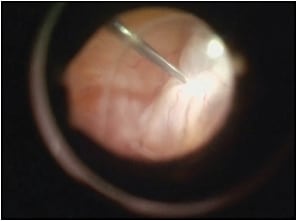

Comparing the failure rates with different treatment methods allowed the study authors to provide recommendations based on RD etiology. Pneumatic retinopexy or scleral buckling (Figure 3) was useful in cases in which a superior atrophic hole induced retinal detachment. However, in the presence of a flap tear, the treatment of choice is scleral buckling, with a lower failure rate than both pneumatic retinopexy and vitrectomy.

Figure 3. A) Intraoperative view during scleral buckling of early onset retinal detachment without PVR. B) Scleral sutures during scleral buckling as seen intraoperatively with a slit lamp.